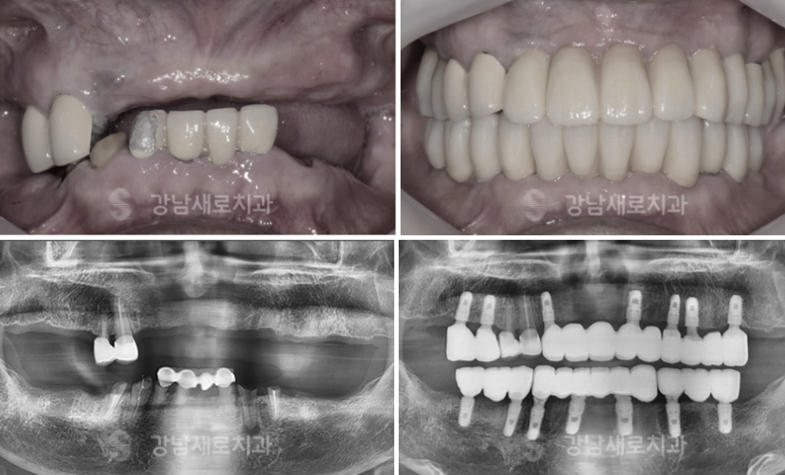

다양한 증례 사람들과 다양한 종류의

임상 경력을 갖추고 있으며 전/문/의 자격을

지닌 다수의 원장님과 이에 대한 노하우가 쌓인

실력 있는 원장님과 모든 절차에 함께하며

1:1 맞춤 보철물로 진료 후 관리까지

체계적으로 도와주고 있었어요.

강남양심치과의 전반적인 모든 절차에

담당의가 함께하여 처음에서부터 끝까지

체계적인 진료를 도와주는 우리는 풍부한

원장님의 실력으로 상태에 맞는

적절한 진료가 가능한 상황이었어요.